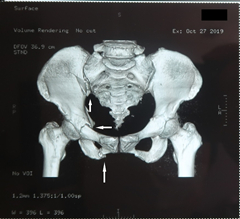

(2)DR片(某某医院,DXXXXXX,2020-5-7):右侧髂骨、耻骨上下支粉碎性骨折,耻骨上下支骨折断端错位,断端形成骨痂,双侧闭孔形态不对称—骨盆畸形愈合。

图2.DR片(DXXXXXX)

被鉴定人的2019年10月27日损伤致骨盆多发性骨折并右骶髂关节半脱位。DR片(2020-5-7)示骨盆畸形愈合(右侧髂骨、耻骨上下支粉碎性骨折,双侧闭孔形态不对称)。